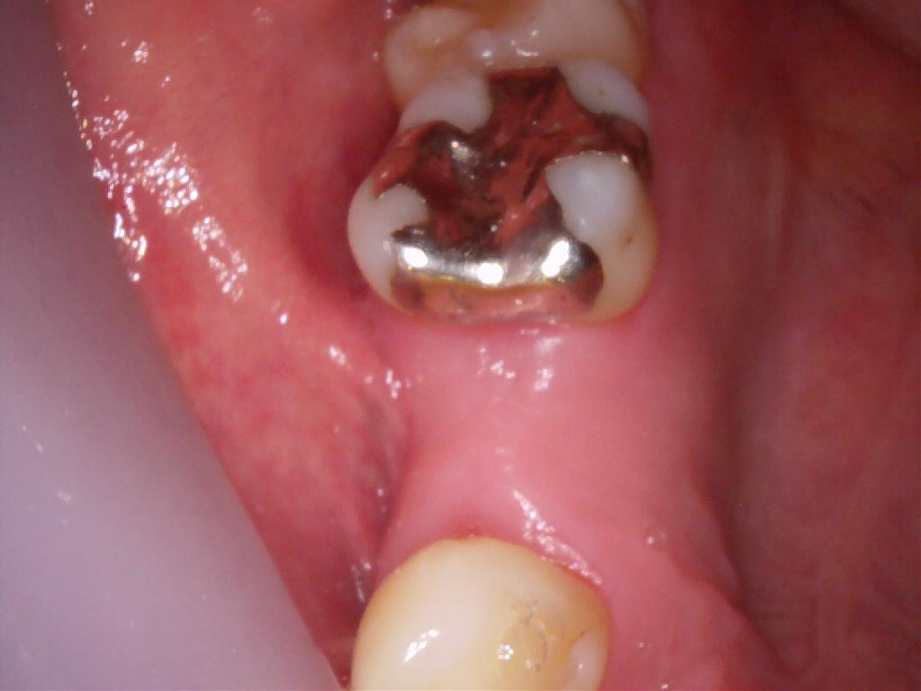

治療前

治療後

レントゲン写真

- 治療名称

- 左上5番欠損によるインプラント治療

- 患者の症状

- 3、4年前に抜歯してからそのままなのでどうにかしたい。

- 治療内容

- まず、CT撮影による精密な骨の分析・治療計画を立てガイドを使いインプラント埋入しインプラントが骨と結合するのを待つ間に仮の歯を入れます。その後本歯を作成して装着しました。

- 治療期間・回数

- インプラント埋入からジルコニアセットまで六か月

- 費用

※自由診療となります - ■総額¥330,000(税込み) ■内訳:埋入(ガイド込み)¥200,000、仮歯¥20,000、被せ物(ジルコニア)¥80,000

- リスク・副作用

- ・術後の腫れ・痛み・出血 ・感染(インプラント周囲炎) ・インプラントの脱落 ・神経損傷によるしびれ ・破損・ゆるみ